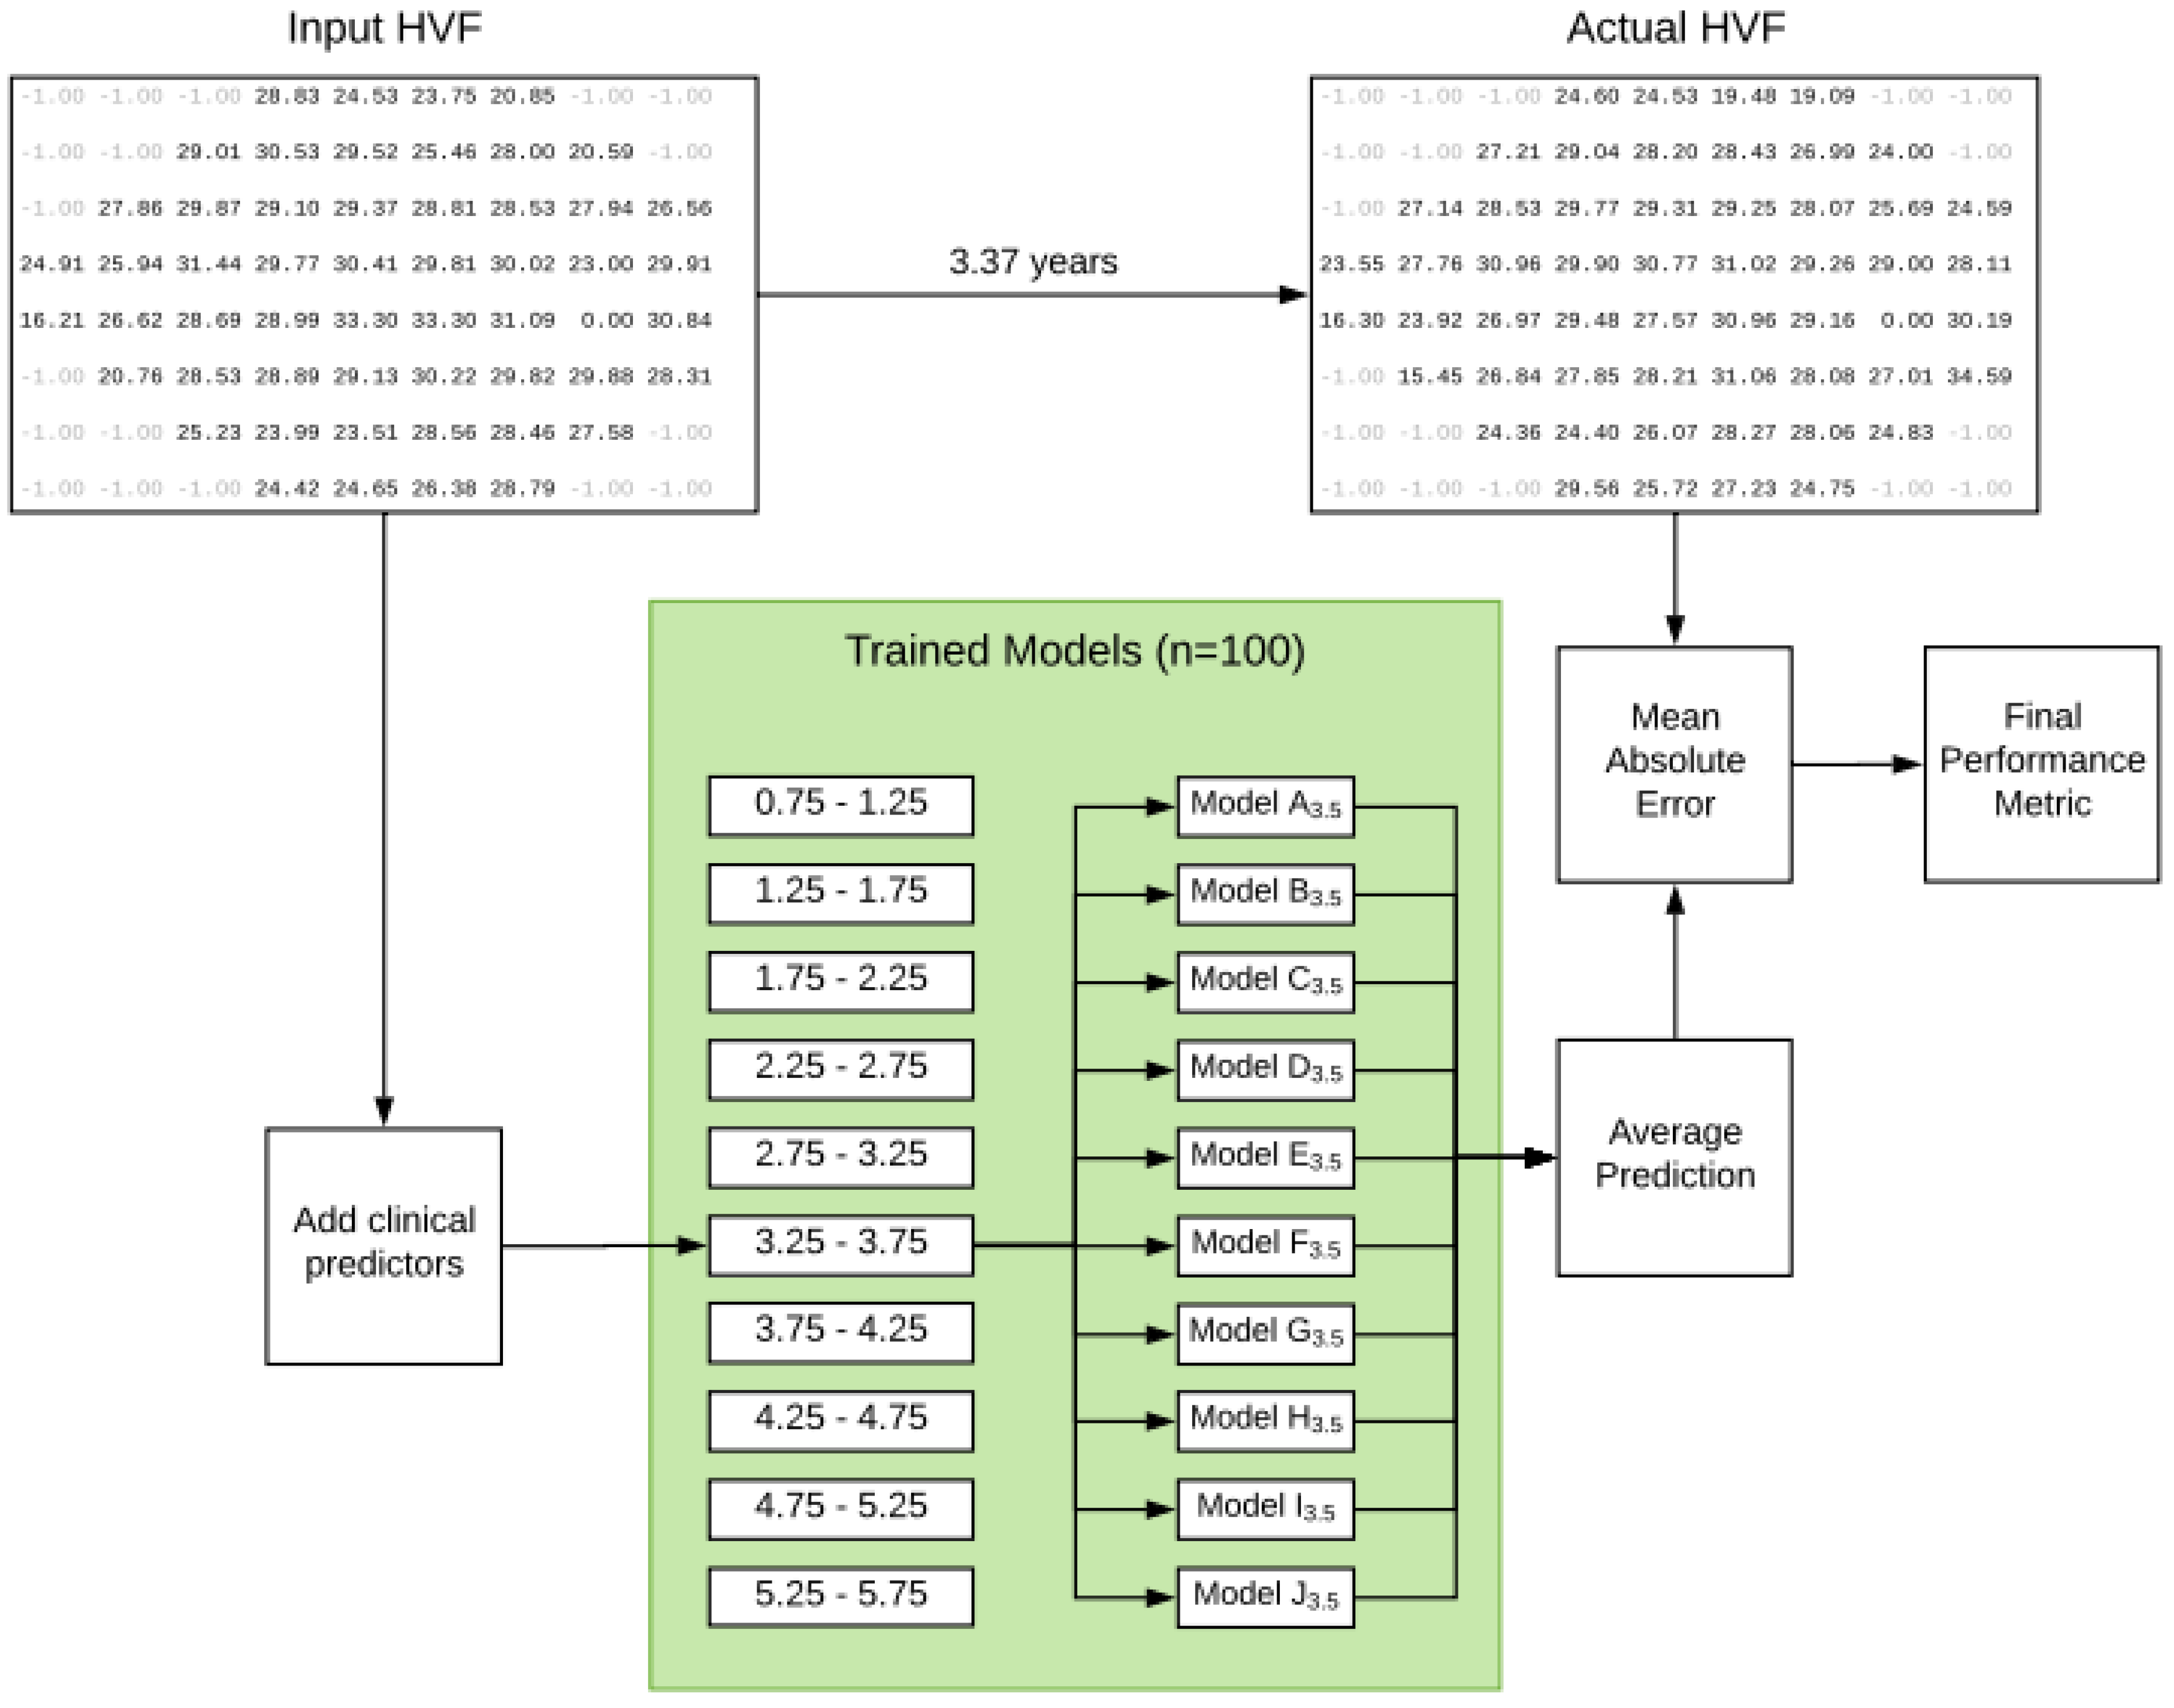

- HMM and R-CNN

- Proposed Model and Experimental Results

3.1. Experimental Results Analyses

3.2. Experimental Results